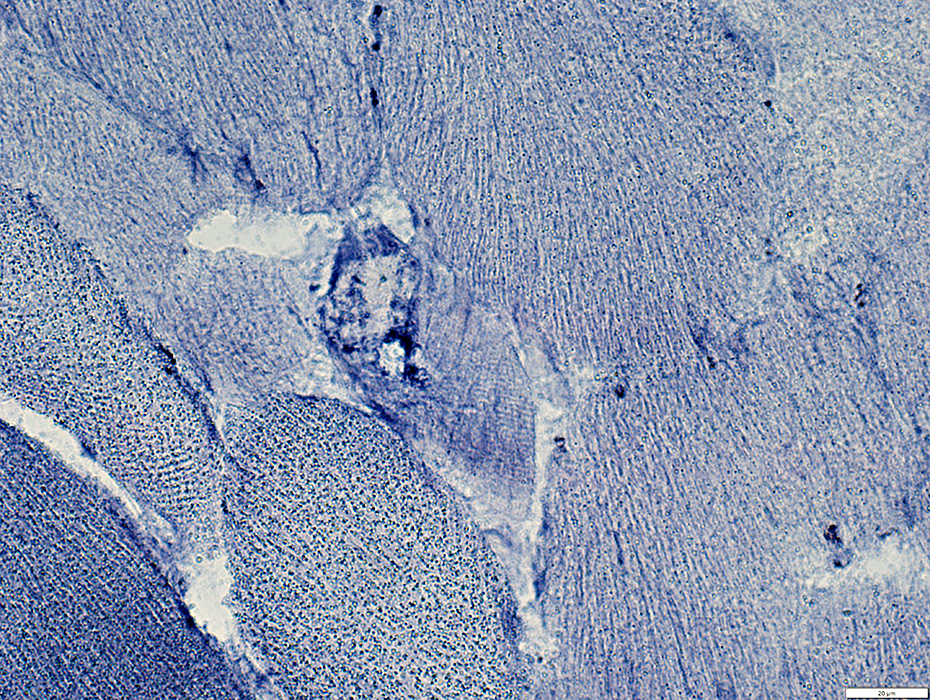

Matrin3 myopathy: AMPDA aggregates in muscle fibers

AMPDA stain